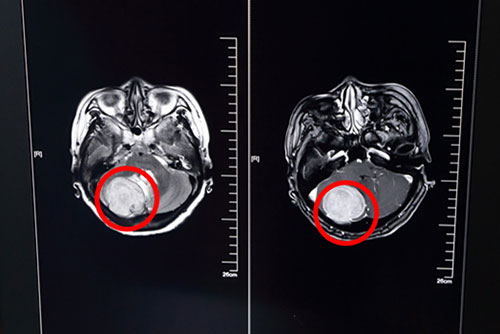

為求進(jìn)一步治療,歐女士慕名來到上海藍(lán)十字腦科醫(yī)院,查頭顱MR平掃加增強(qiáng)示:右側(cè)后顱窩單發(fā)實(shí)性占位病變,增強(qiáng)掃描富血供,病灶與右背側(cè)小腦幕關(guān)系密切。原來,頭痛的罪魁禍?zhǔn)拙谷皇切∧X幕下腫瘤,而且發(fā)現(xiàn)時(shí),瘤體已經(jīng)42*40*45mm大小。

歐女士術(shù)前頭顱MRI影像資料:紅圈內(nèi)白色團(tuán)狀物為42*40*45mm大小腫瘤